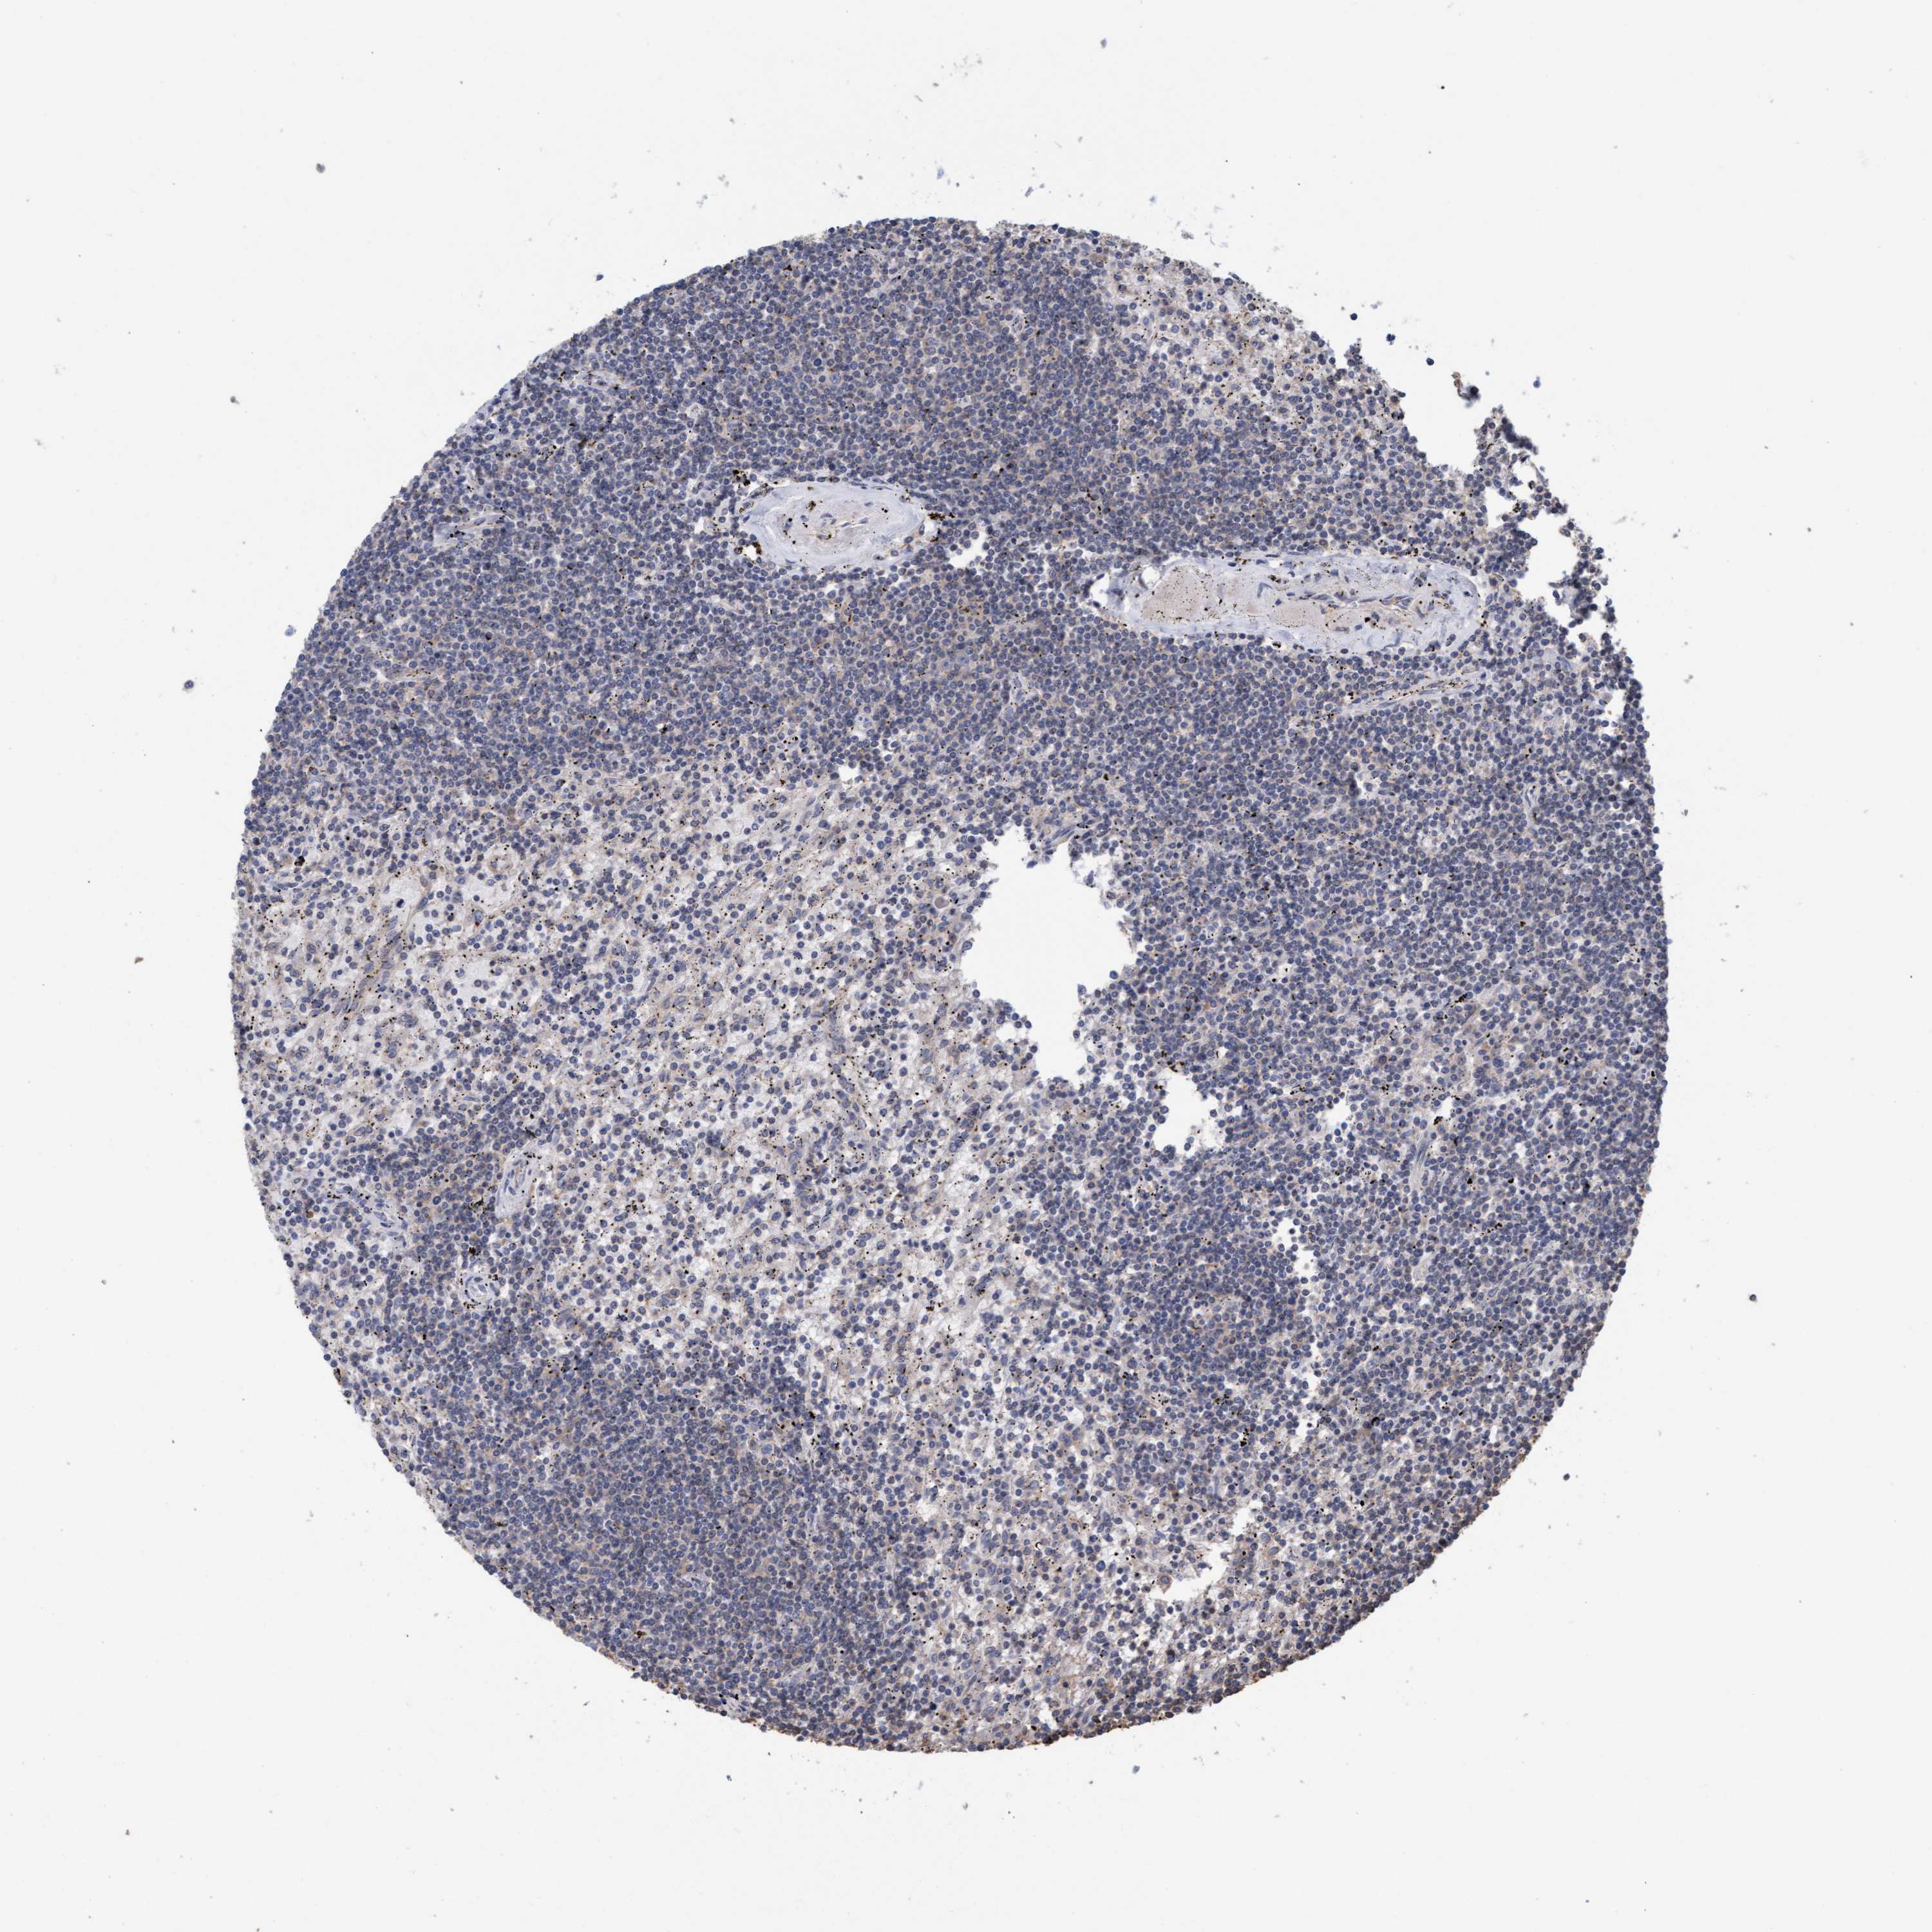

CANCER LYMPHOMA Show tissue menu

LYMPHOMA - Protein expressioni

A mouse-over function shows sample information and annotation data. Click on an image to view it in a full screen mode. Samples can be filtered based on level of antibody staining by selecting one or several of the following categories: high, medium, low and not detected. The assay and annotation is described here.

Each image is clickable and will lead to virtual microscopy that enables deeper exploration of all samples and also displays staining intensity scores, fraction scores and subcellular localization as well as patient and tissue information for each sample.

Antibody HPA022997

Antibody CAB011205

Hodgkin's disease, NOS

Malignant lymphoma, non-Hodgkin's type, High grade

Malignant lymphoma, non-Hodgkin's type, Low grade